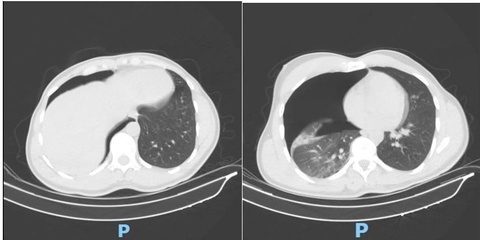

Bệnh viện Bình Dân (TP.HCM) vừa phẫu thuật robot cắt thùy dưới phổi trái cho bệnh nhân mắc phổi biệt lập nội thùy, đây là ca đầu tiên được báo cáo tại Việt Nam.